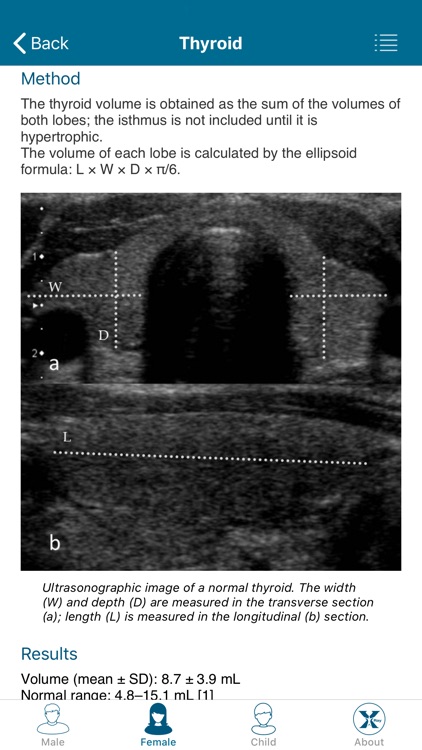

Created by radiologists for all those who practice medical imaging, this application constitutes an atlas of the main measurements in radiology and their normal values based on the most cited literature. It illustrates easy and reproducible methods using different imaging methods.

Created by radiologists for all those who practice medical imaging, this application constitutes an atlas of the main measurements in radiology and their normal values based on the most cited literature. It illustrates easy and reproducible methods using different imaging methods.

The application covers multiple imaging modalities: radiography, ultrasound, CT and MRI. The modules are divided into six sub-specialties: osteoarticular, cervical region, thorax, cardiovascular, abdomen and pelvis.